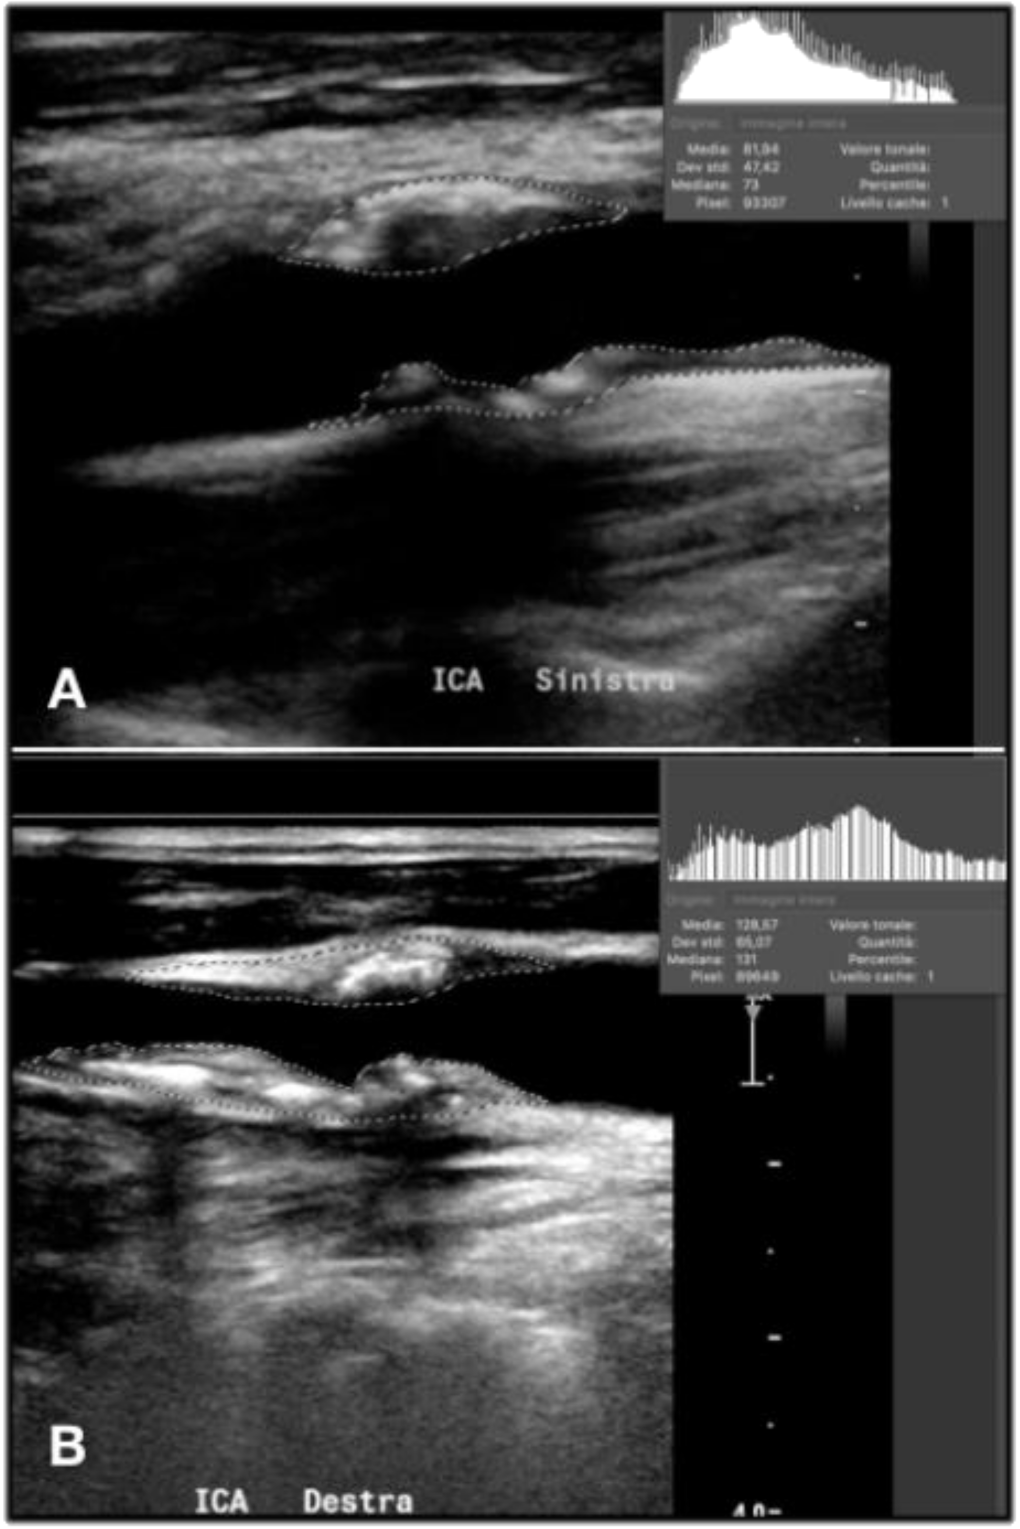

In the case of non-homogeneous plaque, the GSM calculation should be focused on correctly set the adventitia as reference point in the second step and outline the entire plaque in the fourth step (Figure 6).

Figure 6.

The GSM calculation in the case of an heterogenous composition (A) and an irregular profile (B).